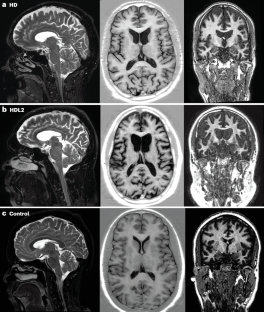

Anderson, D. G. et al. Emerging differences between Huntington’s disease-like 2 and Huntington’s disease: a comparison using MRI brain volumetry. Neuroimage Clin. 21, 101666 (2019).